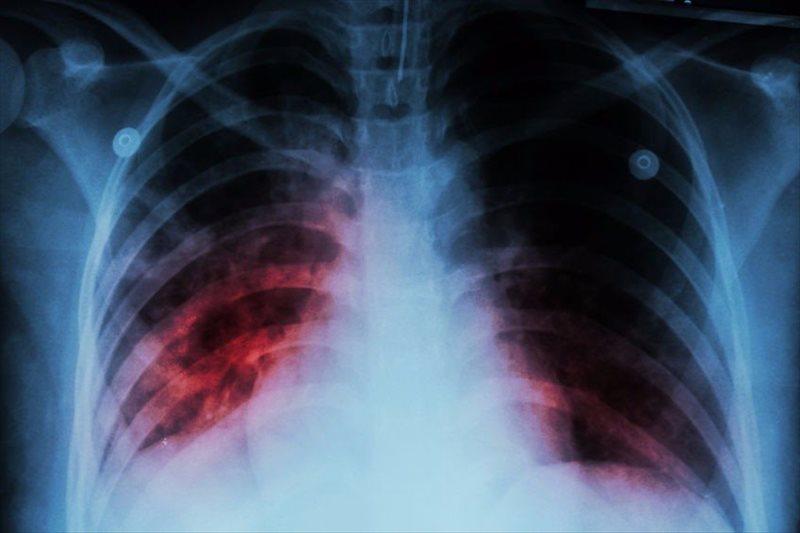

Tuberculosis · tuberculosis (tb) is a disease caused by infection with the bacteria mycobacterium tuberculosis · tb most commonly affects a . Lung – Tuberculosis – NUS Pathweb Source: i1.wp.com